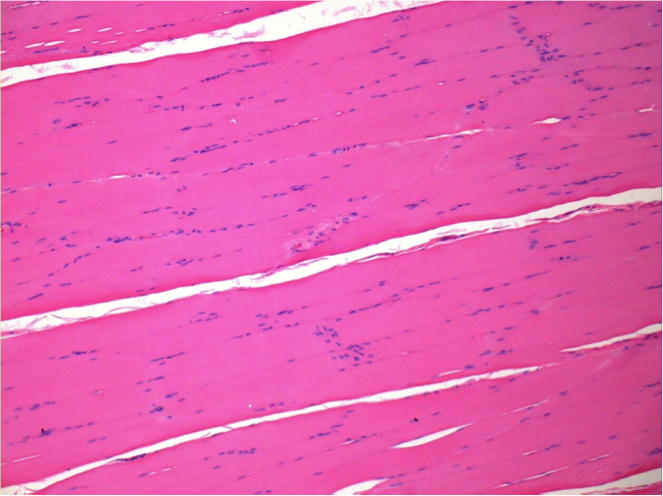

Control

Comment : Nothing to declare after saline solution injection

L:Pretibial-No treatment

R:Pretibial-After 0.1 ml NaCl 0.9% IM